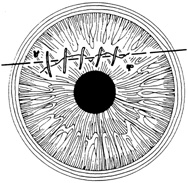

Placement of sutures through the visual axis should be avoided. If it is necessary to pass sutures near the visual axis, they may be placed on each side of, but not directly through, the axis itself. In addition, the bite closest to the visual axis may be made shorter, thus avoiding this area (Fig. 6). A “no-touch” technique also may be used to minimize trauma at the visual axis. With this technique, the eye is secured by grasping the globe with forceps away from the cornea. The suture needle end is then placed perpendicular to the corneal surface, and the needle is rotated through the corneal tissue following the needle's curvature (Fig. 7).8